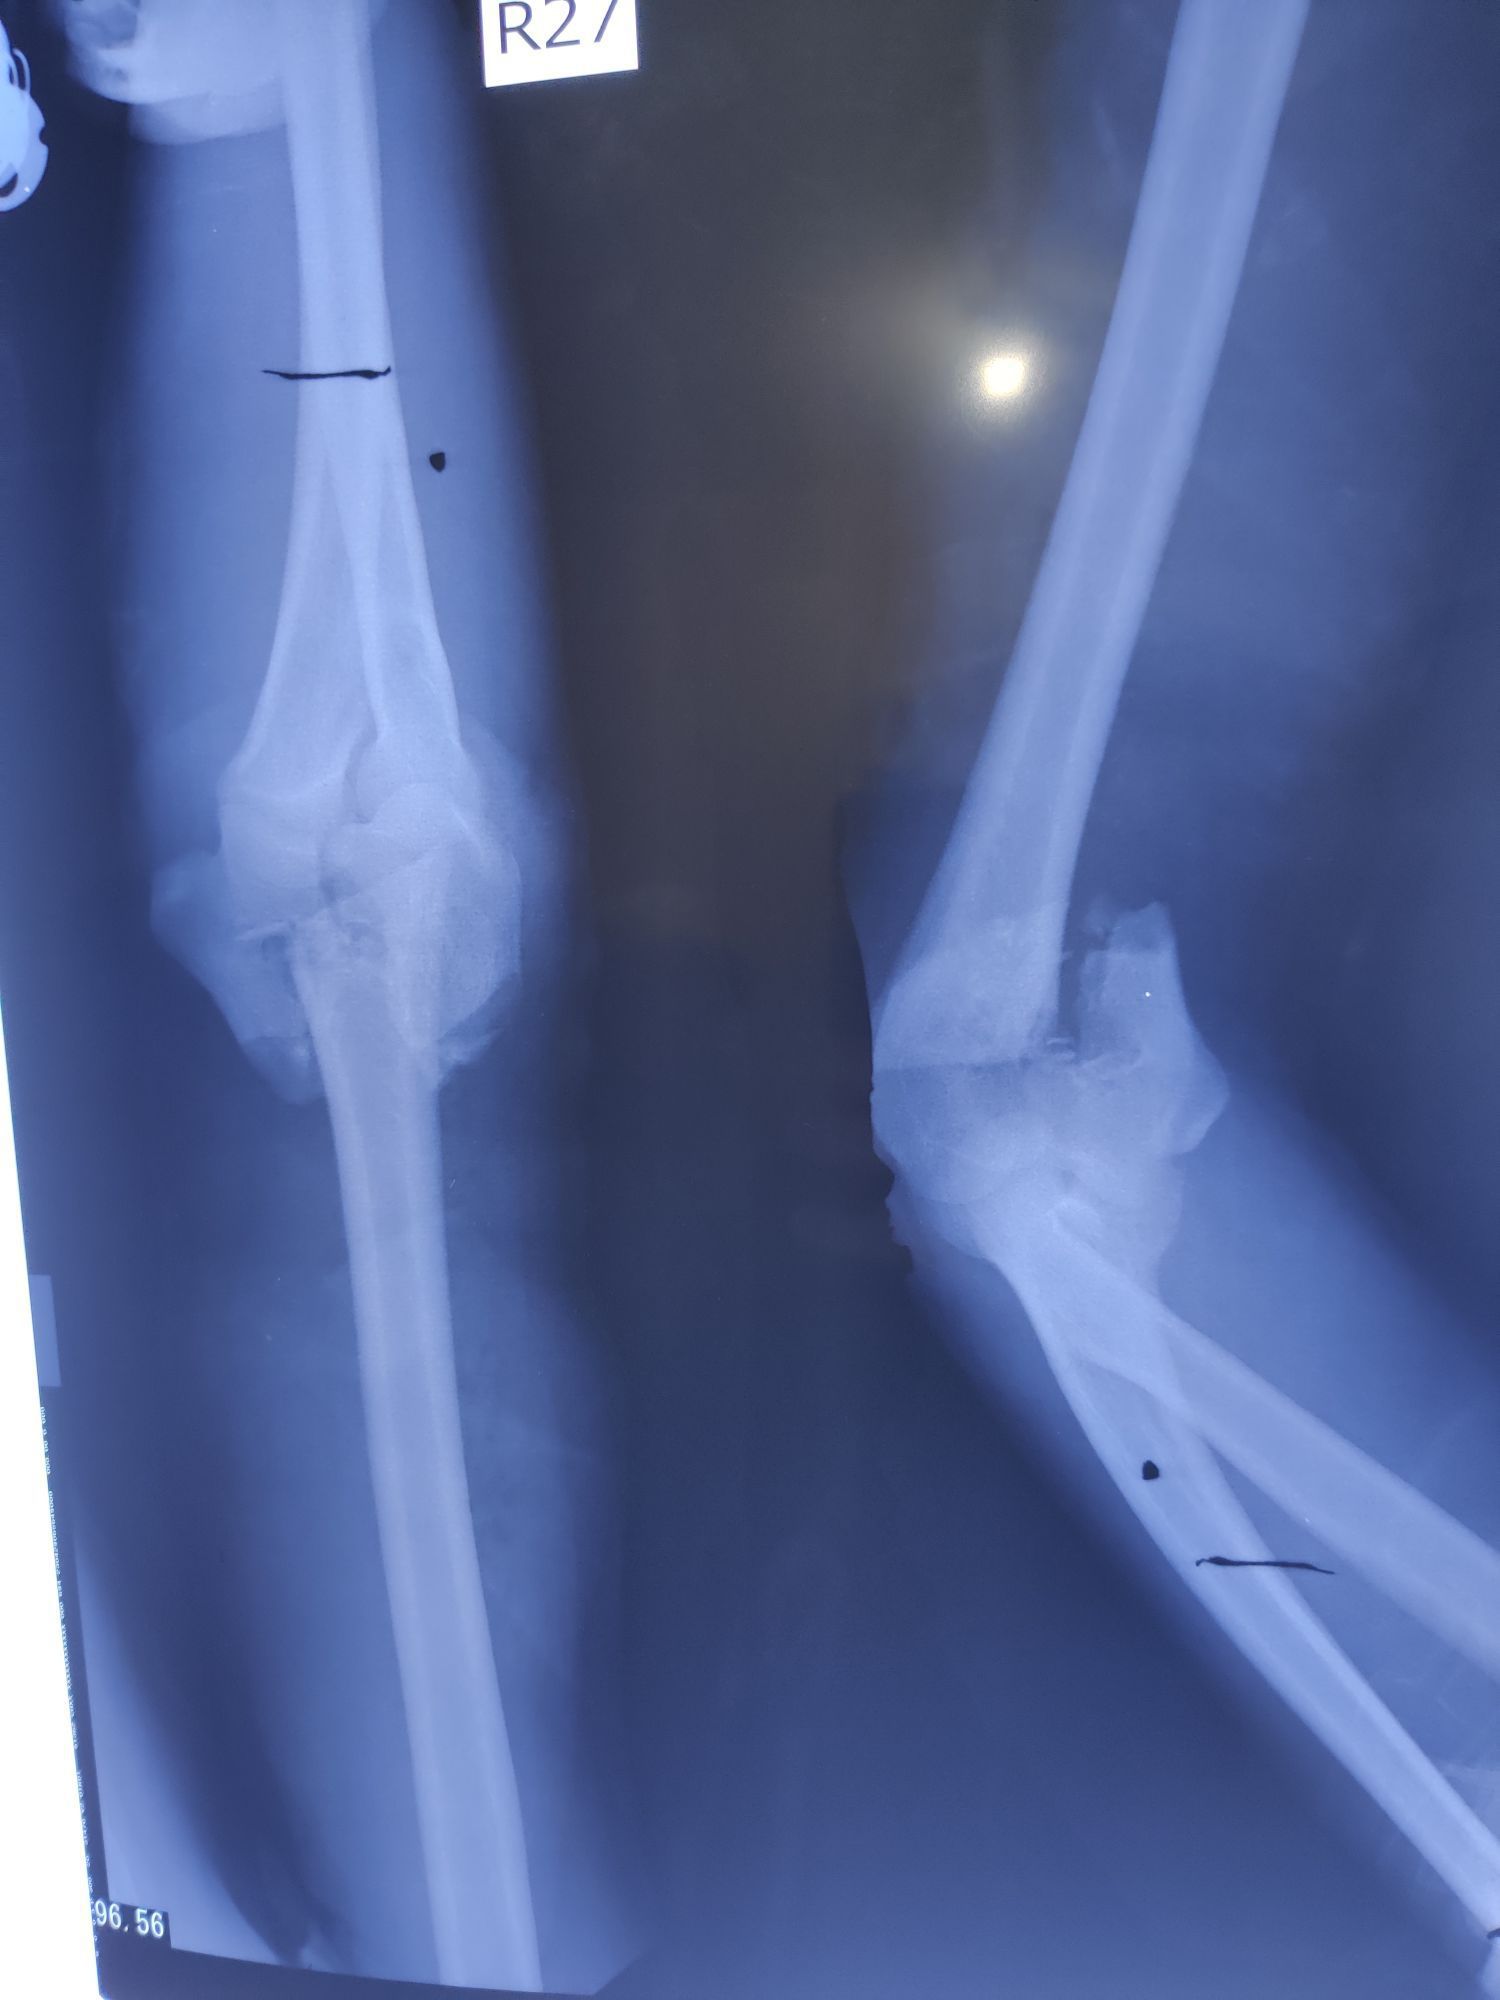

Elbow Fracture

Ortho

Elbow

Rta